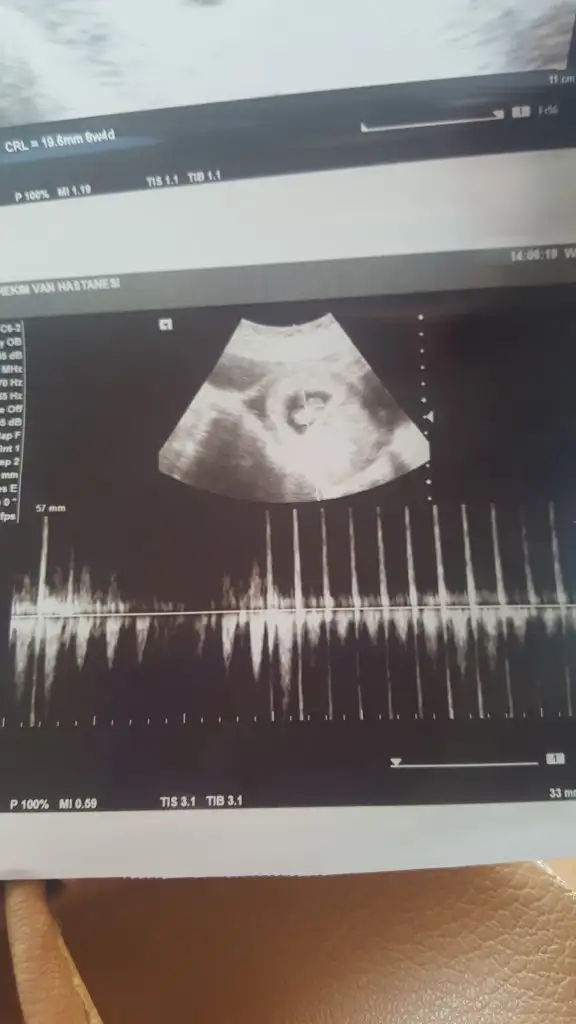

Biliyorum belki çok erken ama merak işte 9 haftadayım herhangi bir tahmin yapabilir misiniz

Haklısın cuma kontrolü varmış ama cinsiyet belli olur heralde 13+ oldu çünküBuna ne tahmin etsem %50 yarı yarıya tahmin olur çünkü çok erken nu bu haftalarda iki tarafa benzer şimdilik erkek yönünde tutmayabilir yuzde verdim